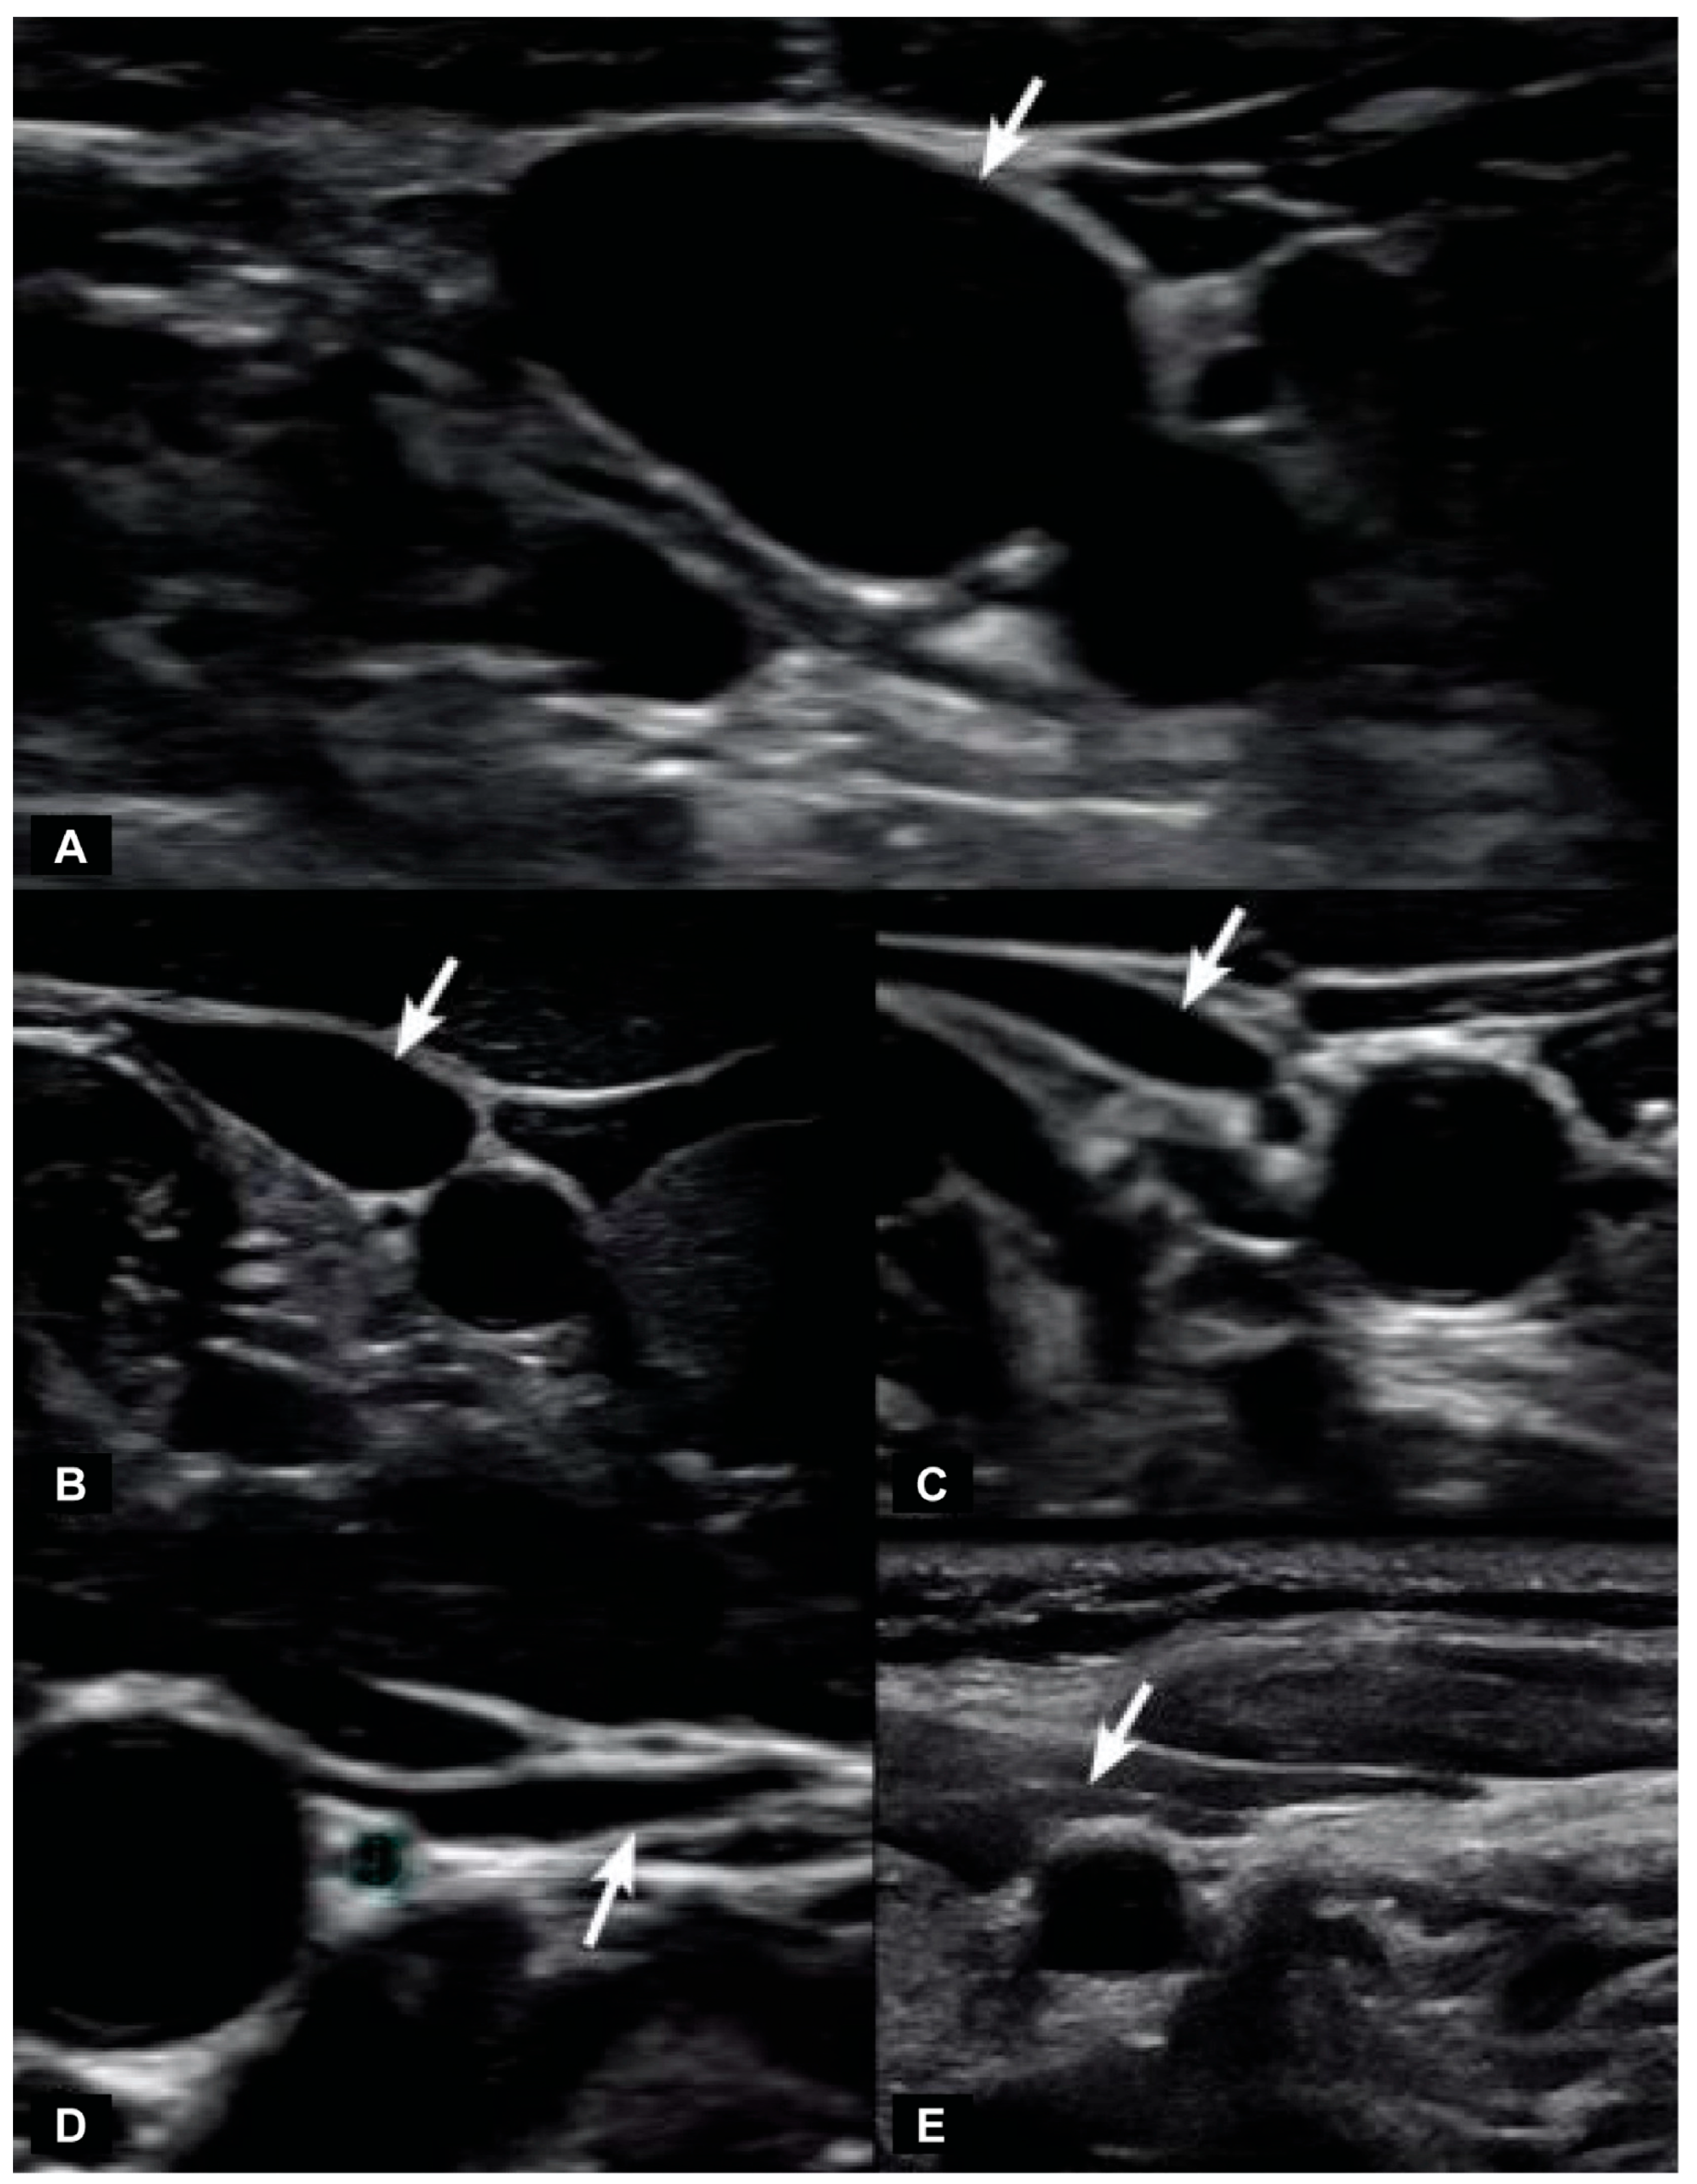

6.2. Dynamic Carotid Sheath Compression

7. Internal Jugular Vein Compression